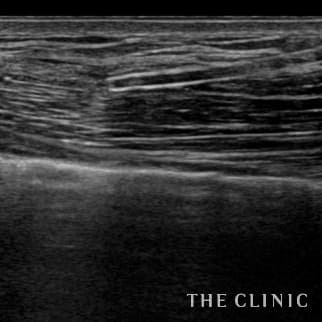

乳腺専用エコーを導入

術前後にエコー検査を行い、手術計画や結果についてを専門的に判断します。